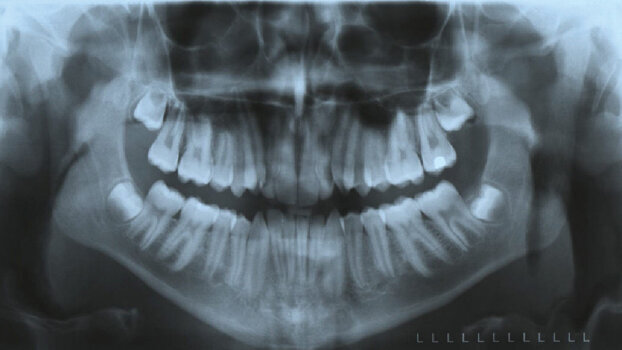

SureSmile patients begin orthodontic therapy with a routine full banding procedure. After three to four months of leveling and aligning, the patient’s mouth is scanned using an OraScanner.

The OraScanner uses non-invasive white light to capture images of the teeth to create a 3-D model of them. This step is the only patient appointment that differs from conventionally treated patients and takes 20 to 30 minutes in the office. An orthodontic assistant trained by OraMetrix staff performs the scan.

From this 3-D model, the occlusion is treated in the virtual world (on the computer). The software developed by OraMetrix to simulate comprehensive orthodontic treatment is a marvel and will be presented in greater detail by Dr Feinberg.

The cost of the equipment includes installation and training; the cost per patient can be passed on in the treatment fee. Many patients understand that new technology costs more. Plus, partnering with OraMetrix will keep you current with the latest and best technology in our profession. The latest upgrade of the SureSmile software introduced CBCT integration for the purpose of creating 3-D virtual models for treatment planning and appliance customization.